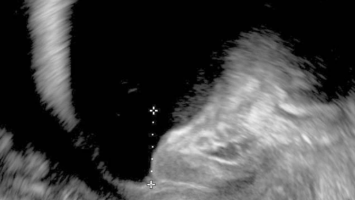

Springer Medizin Podcast - Endometriose/© (M) Willer D. et al. / all rights reserved Springer Medizin Verlag GmbH Logo: Springer Medizin Verlag GmbH, Ärztin misst Blutdruck bei Schwangeren/© Andrey Popov / Stock.adobe.com (Symbolbild mit Fotomodell), Schwangere Frau hält Tablette und Glas Wasser/© NDABCREATIVITY / stock.adobe.com (Symbolbild mit Fotomodell), Justiz/© hawi_101 / Fotolia, CT des Uterus einer 47-Jährigen /© Rizos A et al. | all rights reserved Springer Medizin Verlag GmbH, Gardnerella spp. bedeckte Schlüsselzellen/© Swidsinski A et al. / all rights reserved Springer Medizin Verlag GmbH, Impfung/© Remains / Getty Images / iStock (Symbolbild mit Fotomodellen), Junge Frau sitzt auf Toilette/© Dragana Gordic / stock.adobe.com (Symbolbild mit Fotomodell), Spritze wird aufgezogen/© scyther5 / Getty Images / iStock, Ultraschall der "kissing ovaries" bei Endometriose/© Willer D. et al. / all rights reserved Springer Medizin Verlag GmbH, Ärztin führt Ultraschall bei einer Frau durch/© satyrenko / stock.adobe.com (Symbolbild mit Fotomodellen), Doxy-PEP/© Tobias Arhelger / stock.adobe.com, Junge Frau zur Beratung bei Ärztin/© demaerre / Getty Images / iStock (Symbolbild mit Fotomodellen), Schwangere macht Gymnastik/© fotostorm / Getty Images / iStock (Symbolbild mit Fotomodell), Junge Patientin im Gespräch mit einer Ärztin/© FatCamera / Getty Images / iStock (Symbolbild mit Fotomodellen), Urogenitale Fistel bei einer 36-jährigen Patientin/© Lautenschlager S et al. / exklusiv lizenziert an Springer-Verlag GmbH Austria, ein Teil von Springer Nature 2024, CT bei endometrioidem Karzinom/© Kuzinska MZ et al. / all rights reserved Springer Medizin Verlag GmbH, Frau nimmt Diaphragma in der Hand/© AndreyPopov / Getty Images / iStock (Symbolbild mit Fotomodellen), Ein Abstrich vom Gebärmutterhals wird auf ein Objektivträger geschmiert/© Tatiana Buzmakova / Getty Images / iStock (Symbolbild mit Fotomodellen), Frau nutzt Pen am Bauch/© bung / Stock.adobe.com (Symbolbild mit Fotomodell), Reife Eizelle im Mikroskop/© S. Al-Hasani, Podcast mit Partnern - Roche STI/© (M) Aleksej / stock.adobe.com; Logo: Springer Medizin GmbH, Titelbild Kongress Kompakt EADV 2024/© Hintergrundbild: gnoparus / stock.adobe.com, Search Icon, Paar schaut glücklich auf Schwangerschaftstest/© Andrii Zastrozhnov / Stock.adobe.com (Symbolbild mit Fotomodellen), ZFA TALKS - Depression/© (M) seb_ra / Getty Images / iStock (Symbolbild mit Fotomodell) Logo: Springer Medizin Verlag GmbH, Ältere Frau fasst sich an die Brust/© Jelena Stanojkovic / Stock.adobe.com (Symbolbild mit Fotomodell), Person setzt DNS-Probe in Maschine ein/© Vit Kovalcik / stock.adobe.com